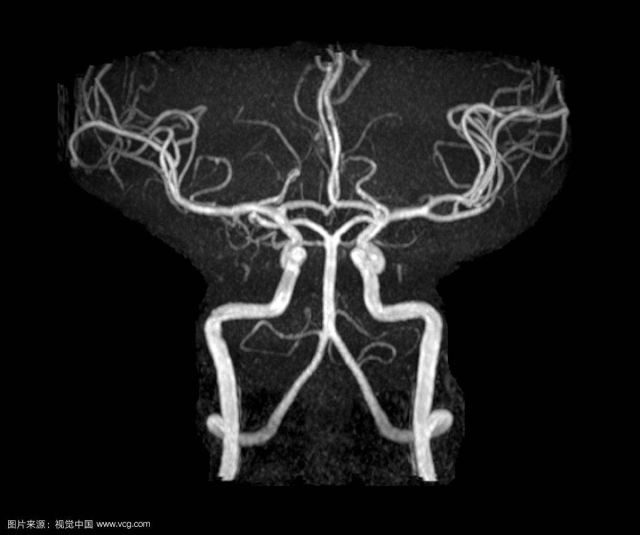

DSA:脑血管诊断的金标准,可显示动静脉以及血流动力学,并可三维成像。缺点是具有一定的有创性,价格较贵。

CTA:静脉注入造影剂后CT血管成像,显示动脉。显影比较精确。

MRA:无需注入造影通过核磁共振检查动脉血管和静脉。作为脑血管病筛查手段,内科常用。

血管成像分CTA,磁共振和DSA三种血管成像,这三种血管成像的主要作用是真真正正检测有没有动脉狭窄,并指导治疗方向。